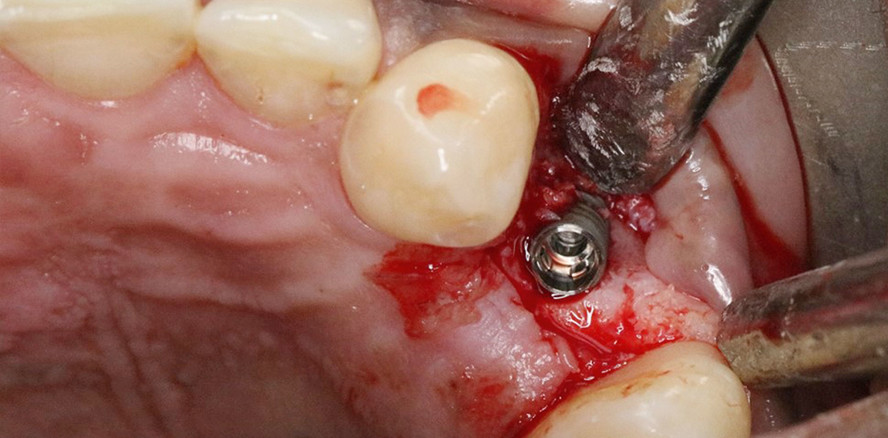

Das Implantat wurde primärstabil inseriert. Da sich die bukkale Knochenwand während des Implantatvorgangs als nicht ausreichend erwies, war eine laterale Augmentation (cerabone® Granulat 0,5–1 mm, botiss Biomaterials) erforderlich.

Anschließend erfolgte die Insertion des Implantats. Idealerweise sollte die Implantatschulter im ästhetisch relevanten Bereich circa 3–4 mm subgingival vom voraussichtlichen Gingivarand positioniert werden.

Das hier verwendete Implantat kann entweder manuell oder mithilfe eines Winkelstücks eingesetzt werden. Es wird eine maximale Drehzahl von 15/min empfohlen. Dabei ist darauf zu achten, das gebohrte Loch am blauen Transferteil exakt orofazial auszurichten.